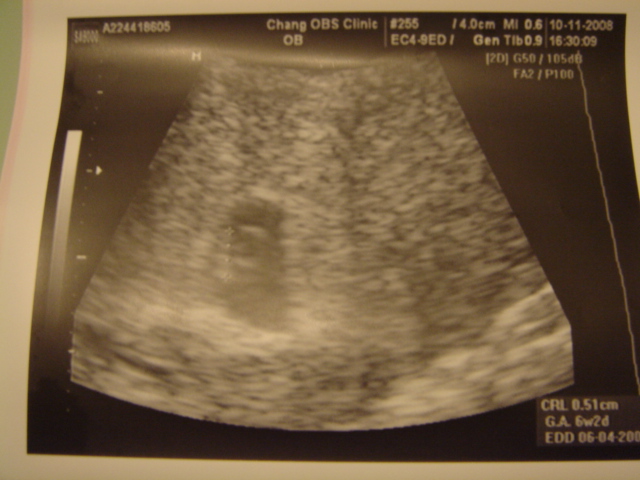

從九月中起 幾乎每週都到診所報到

每次報到 心情總是複雜的

擔心小bb沒有繼續長大 (因為曾經有過小產的經驗)

讓我每天都擔心又害怕

但是這次的檢查

讓我好開心喔~

因為小bb心動了

看著他心動的感覺真好